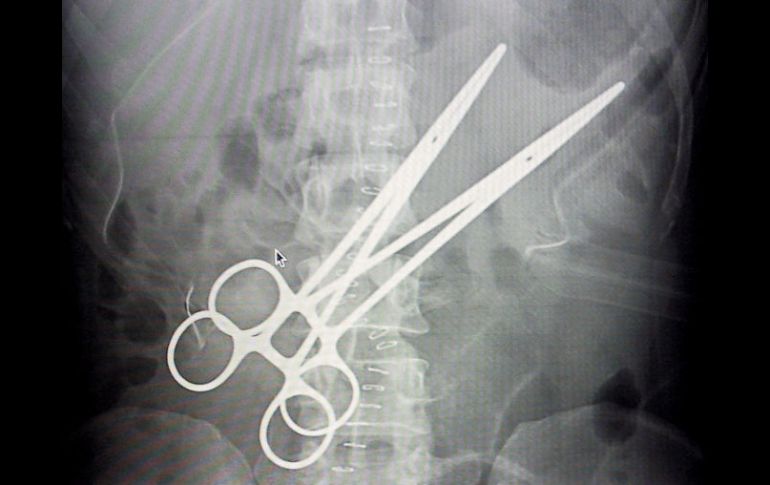

Tecnología | El instrumento estuvo dentro de la joven por más de una década Retiran a boliviana pinzas de 16 centímetros que médico dejó en su abdomen Las pinzas quirúrgicas, que en las ecografías parecen tijeras, estuvieron encapsuladas durante todo el tiempo por una carnosidad que protegió la vida de la paciente Por: EFE 21 de enero de 2012 - 18:44 hs El médico que olvidó las pinzas fue denunciado por lesiones gravísimas y debilidad permanente a la mujer. EFE / LA PAZ, BAJA CALIFORNIA SUR (21/ENE/2012).- Dos médicos retiraron a una mujer boliviana unas pinzas de 16 centímetros que estuvieron en su abdomen durante 16 años, desde que fue sometida a una cirugía de vesícula en la ciudad central de Cochabamba, informó hoy su abogada. La letrada Jhazmina Loza dijo a Efe que su clienta, cuyo nombre prefirió no revelar, fue sometida el miércoles a una cirugía en la que dos médicos forenses, en presencia de un policía y funcionarios de la Fiscalía, extrajeron las pinzas, que estaban partidas en el abdomen de la mujer, de 53 años y condición humilde. Las pinzas quirúrgicas, que en las ecografías parecen tijeras, estuvieron "encapsuladas" durante todo el tiempo por una carnosidad que protegió la vida de la paciente, lo cual mostró a los médicos "lo maravilloso del cuerpo humano", dijo la abogada. "Ella jamás se imaginó que tenía un instrumento quirúrgico olvidado. Ha dejado de trabajar, perdió paulatinamente la fuerza, no podía estar parada, ni sentada, no podía dormir y nunca se dio cuenta de lo que tenía", añadió Loza. El médico que olvidó las pinzas fue denunciado por lesiones gravísimas y debilidad permanente a la mujer, por causar incapacidad laboral y poner en riesgo su vida. Temas Sanidad Ciencia médica Curiosidades Lee También ¿Por qué duelen las manos cuando hace frío? Lo MEJOR que se debe hacer con un celular mojado Estos son los riesgos de tener una vida sedentaria Así ha bajado la afiliación de trabajadoras del hogar en el IMSS Recibe las últimas noticias en tu e-mail Todo lo que necesitas saber para comenzar tu día Registrarse implica aceptar los Términos y Condiciones